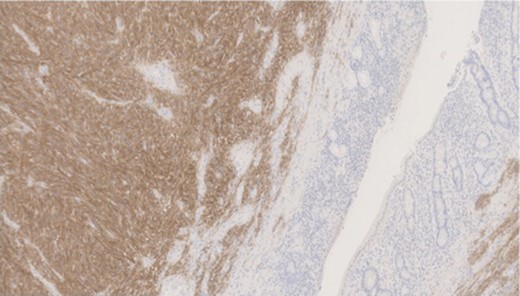

Pathology—GIST of spindle cell type (Figs 3 and 4), 90 mm in size, with complete local excision. Mitotic count—3 per 5 mm square. CD117 (Fig. 5) and DOG1 (Fig. 6) positive staining giving a prognostic group of moderate risk (Miettinen’s classification) of progressive disease. It is widely accepted that Interstitial Cells of Cajal (ICC) are pace maker cells of the gut and probable progenitor cells of GIST. Hyperplasia of ICC can be seen in cases with NF1, however, in this case this could not be shown in the background bowel (Fig. 7).

Higher power view showing the spindle appearance of tumour cells.